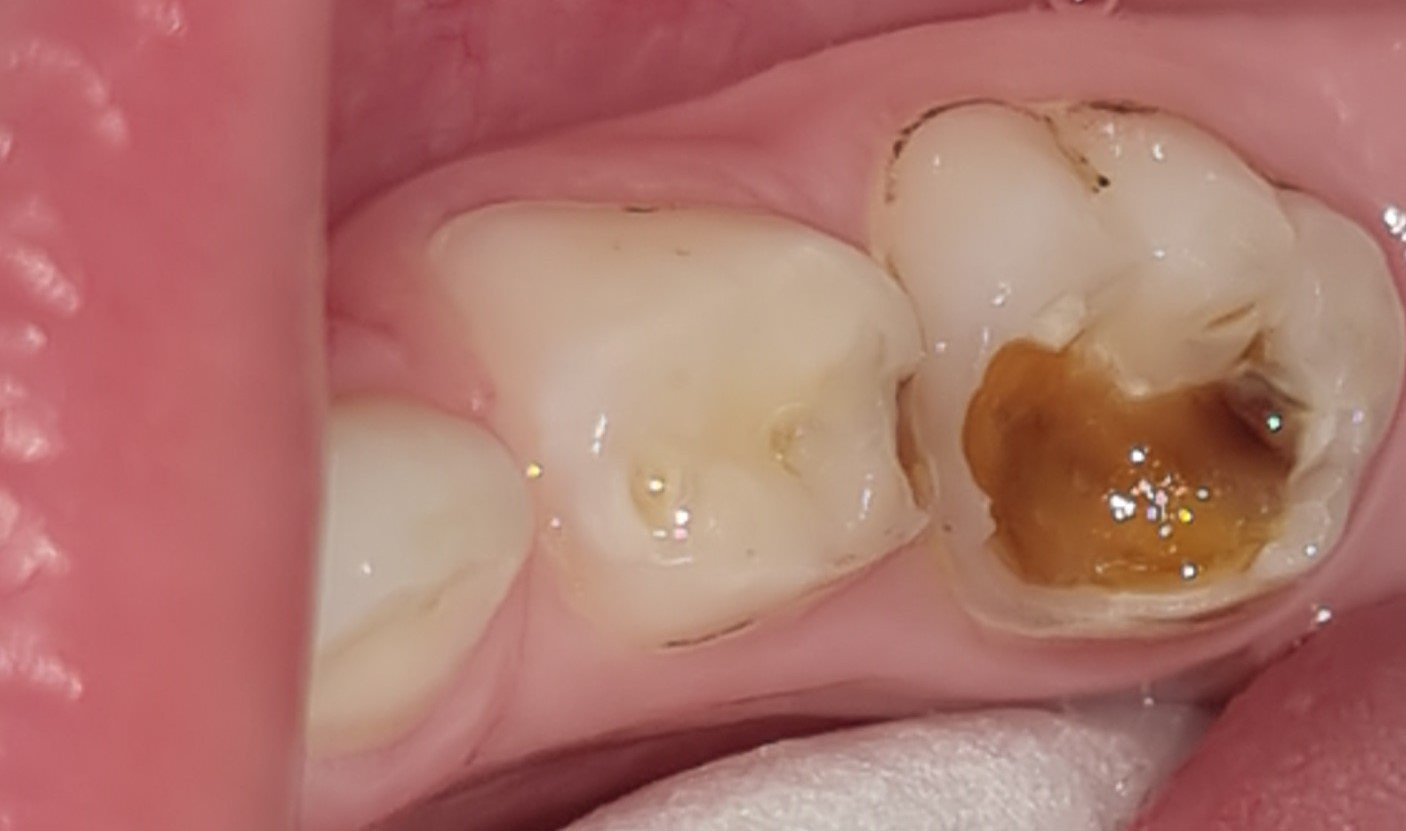

In the BRIX3000® group, the manufacturer’s guidelines were followed; BRIX3000® was applied to the cavity using a microbrush and left in place for approx. 2–3 min. Subsequently, the infected dentin that had dissolved was removed with a spoon excavator, without applying pressure or making incisions. In instances where the cavity was still occupied with infected dentin, the implementation of an additional layer of the agent might have been necessary (Figure 2). When sound dentin of the cavity was reached and all infected dentin was removed (Figure 3), the stopwatch was halted and the duration of the procedure was recorded in the case sheet, signifying the completion of the caries removal process.